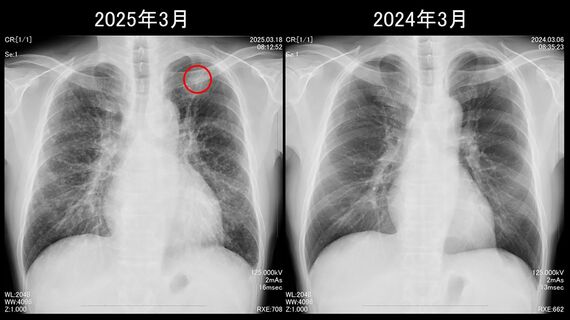

そして3月18日。毎年行っているがん検診で肺がんが見つかった。肺のX線写真には、左の肺尖部(せんぶ)というろっ骨の下に白い影が写っていた。

また、両肺には白い斑点がいくつも確認できた。その日の午後にCTを撮るなどいくつかの精密検査を受けた結果、白い影は腺がんというタイプの肺がんで、リンパ節や骨、脳にも転移していることがわかった。

1年で肺がんが転移する? これって見落としでは? そう思うかもしれない。だが、松田さんは去年も自身で肺のX線写真をチェックし、影が“見えていない”ことを確認している。